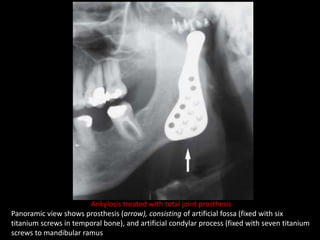

Ankylosis treated with total joint prosthesis

Panoramic view shows prosthesis (arrow), consisting of artificial fossa (fixed with six

titanium screws in temporal bone), and artificial condylar process (fixed with seven titanium

screws to mandibular ramus